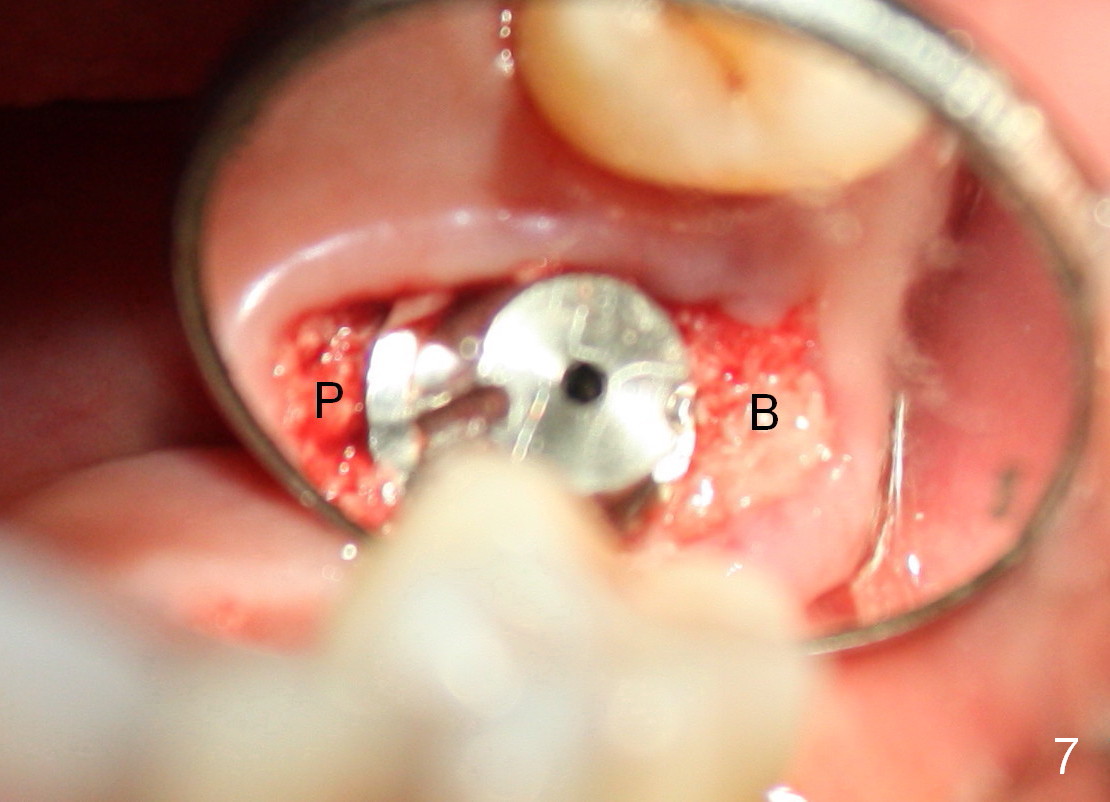

The large implant obliterates the socket mesiodistally (Fig.7); the buccal (B) and palatal (P) gaps are filled with bone graft, which is held in place by an immediate provisional.

The tissue-level implant is placed subgingivally (mesially); insertion torque is 15 Ncm. The same diameter cylindrical implant with larger surface area may achieve higher insertion torque with supragingival margin. The latter is easy for restoration.